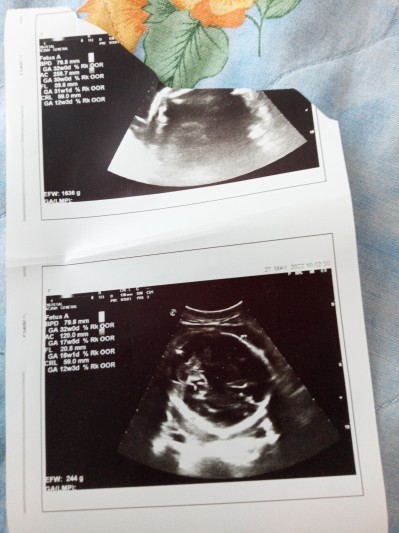

31+4 günlük haftalık dün doktora gittim de bunu verdi boyu kaç cm nasıl anlicam

Gebelik haftası 31+4

Boyu 50 cm canım orda crl yazıyor o boymus :Dultrasina göre tam 32 haftalık

Az mı acaba boyu nasıl ki bişe de demiyorlar boyunu sordum napcan haftası ile uyumlu dedi bari kilosunu söyleyin dedim 1636 gr dedi zorla soru sorma kafam karıştı diyo

YÖK kiz Yeni Doğanlar 50 oluryor genelde maşallah sadece bişey anlamadım orda niye 12 haftalık yazıyor oltrason foto da

Bu kesin devlet devletin ultroson cihazı böyle bide anneye bir şey demiyolar özel herşeyi ölcuyolar bn ilk foroyu görünce kesin haftası küçük dedim bi baktım 30 hafta ve foto böyle Allah'ım iyi doktorlarla karşılaştırsın kuzum keşke yardım edebilseydim ama bnde anlamadim 12 hafta 17 hafta felan da yaziyor

Alttaki başkasının ki birgün banada öyle oldu başkasına vermeyi unuttuğu cihazda kalan kağıtla benimki birlikte çıkmıştı üstteki senin

Elindeki usg sadece kafa yapisinin usgsi daha ölçüm yapmamis boyunu. Beyin gelisimine bakmış. Yani usgde yazan fl ile 7 carpsanizda sizinki cikmaz şuan.